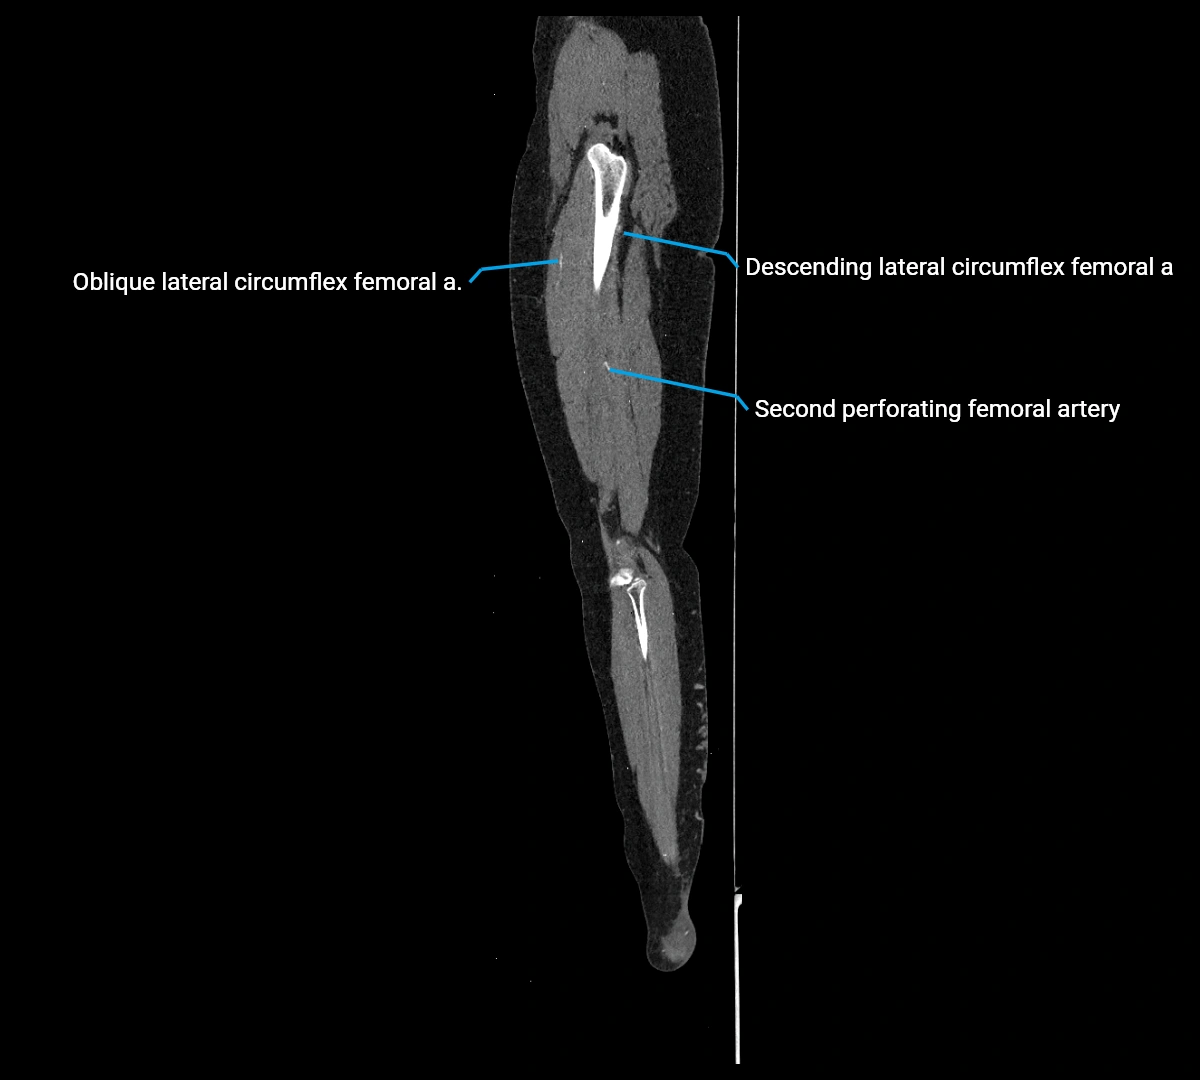

CT images

image

Contrast-enhanced CT (CTA):

• Gold standard for abdominal aortic imaging

• Provides excellent detail of lumen, wall, aneurysm, thrombus, and branch vessels

• Multiplanar and 3D reconstructions help in aneurysm measurement, stent graft planning, and dissection evaluation